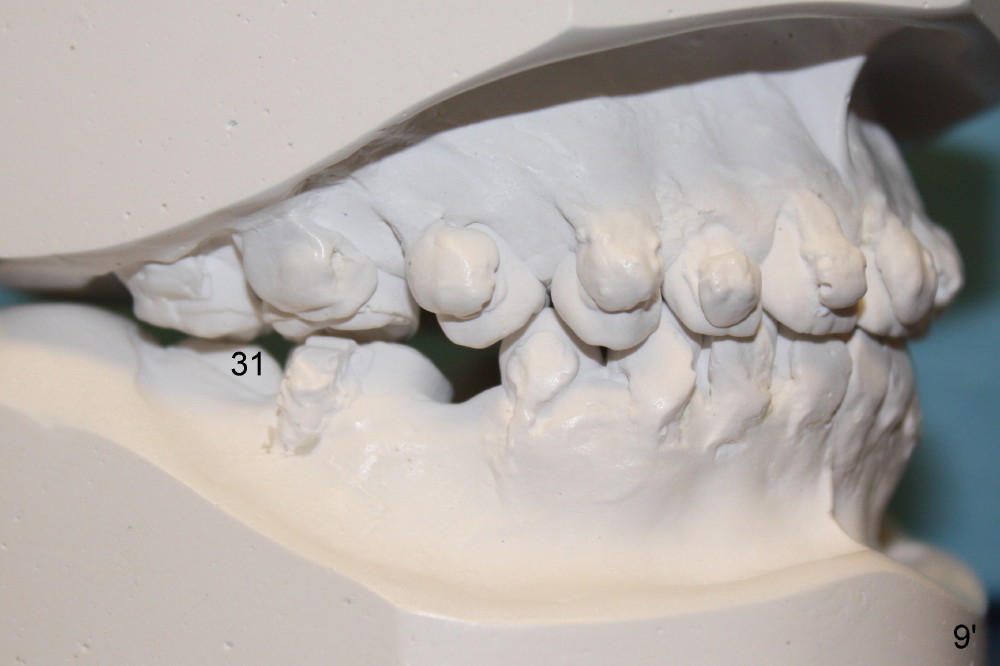

A 13-year-old Asian girl seeks orthodontic treatment for crowding. The lower 2nd bicuspids are congenitally missing (Fig.1,8), whereas the upper right one rotates 180° and the upper left is partially impacted (Fig. 1, 7). The lip muscles strain when the lips close (Fig.3). Orthodontic treatment started with extraction of four affected teeth (#4,13, K and T) 6 months ago. .018' niti wires are being used. Dental midlines do not coincide preop and intraop (Fig.4,4'). Pre-op front view shows that the upper dental midline coincides with the facial one (Fig.1'). There is Class I canine and molar relationship on the right (Fig.5,5',9,9'); open bite on the left (Fig.6,6',10,10').

Next steps: 1. Use elastics to close open bite on the left and to upright #31 (linguoversion, probably #18 to lesser degree) (Fig.8,8',9,9'); 2. Shift the lower midline to the left before closing 2nd bicuspid spaces. What is the best way to close spaces? Power chains for both arches or closed coil springs for upper and loop for lower (which is used for Tiffany Yue)? Since intraop profile is acceptable (Fig.2',3', as compared to Fig.2,3 (preop)), molars will be mesialized.

Update: The left open bite was closed less than one month by wearing elastics between upper and lower teeth (Fig. 6'''). The occlusal plane and midline improve (Fig.4''). Wires have gradually changed to .016x.016, .016x.022 and now .018x.025 with power chains. All the spaces are closed except the one in LR (Fig.7''-10''). What I cannot accomplish is to fix meisal (Fig.5'' (white line), 9'') and lingual (Fig.8'' arrows) inclination of LR molars, although elastic is instructed to be placed between UR7 buccal and LR7 lingual. The rectangular wires could be twisted to fix lingual inclination. Which should be done first: LR space or LR molar inclination? Click each figure for magnification.